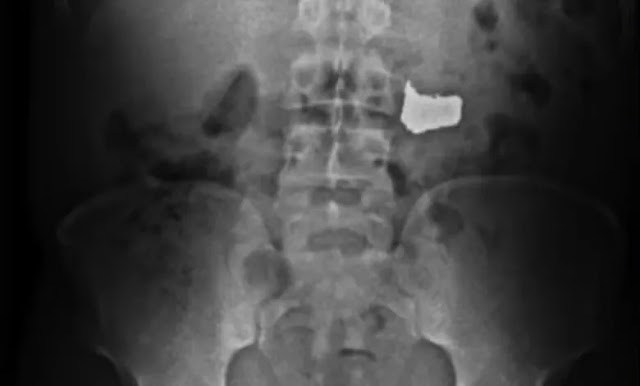

Segundo o órgão, antes de ser detido, na frente dos militares, o homem engoliu a corrente para tentar escapar da prisão. Ele foi levado, inicialmente, para a Unidade de Pronto Atendimento (UPA) dos Barris, onde passou por exames. Através de raio-x, foi atestada a presença da corrente no organismo do suspeito, que não teve nome divulgado.